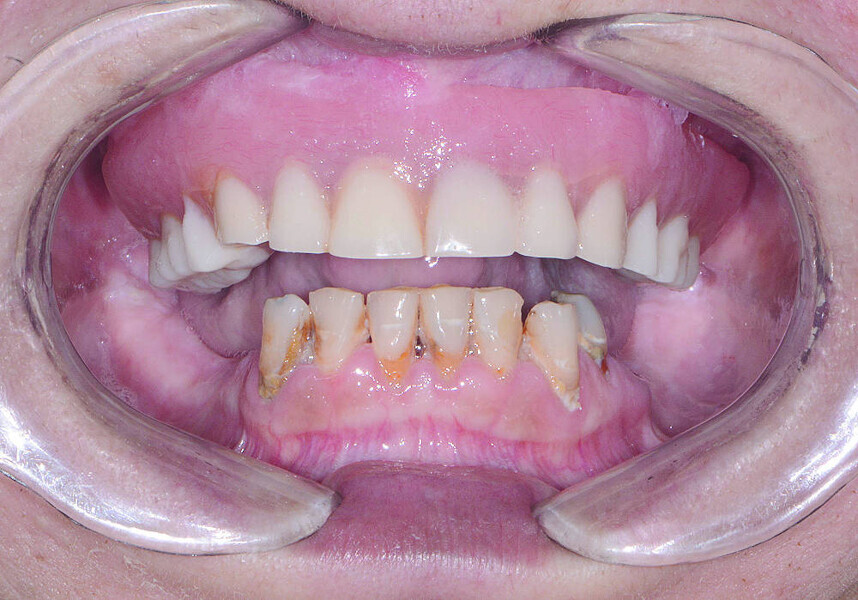

Fig 3 Présentation du traitement de l’arcade maxillaire

Fig 4 Présentation du traitement de l’arcade mandibulaire